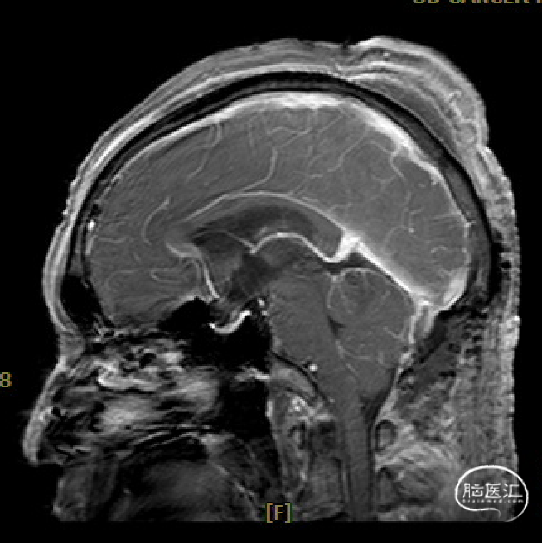

患者5年前无明显诱因出现阵发性头晕,无明显头痛、恶心呕吐等不适,开始未予重视,2022-7-19出现头晕加重,伴视力下降,遂于2022-7-24在当地医院行颅脑MRI提示:松果体区肿瘤伴梗阻性脑积水。

于该院在2022-7-27全麻下行松果体区病灶部分切除活检+神经内镜下第三脑室底造瘘术,术后由于取出肿瘤组织少,未能明确病理结果。患者术后恢复顺利,为进一步治疗就诊于我院。

枕下后正中开颅经幕下小脑上入路松果体区肿瘤切除术。

术前MRI与术后复查MRI对比